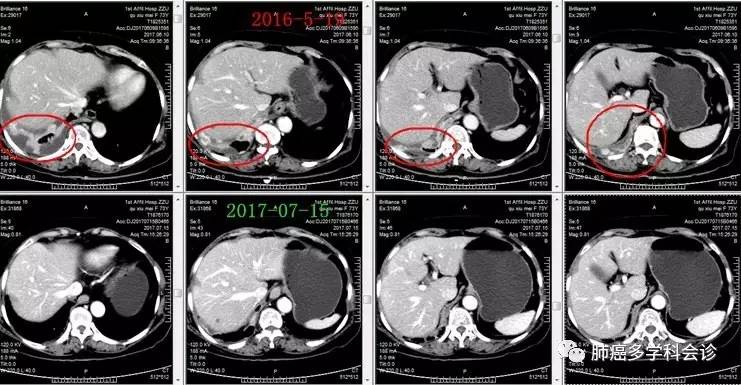

微信图片_20170721110259.jpg诊断为“肾癌多发转移”,阿昔替尼 5mg 每天 2 次连续口服 1 月后,复查CT:右肾肿块明显缩小,双肺转移灶也明显缩小或消失。微信图片_20170721110302.jpg